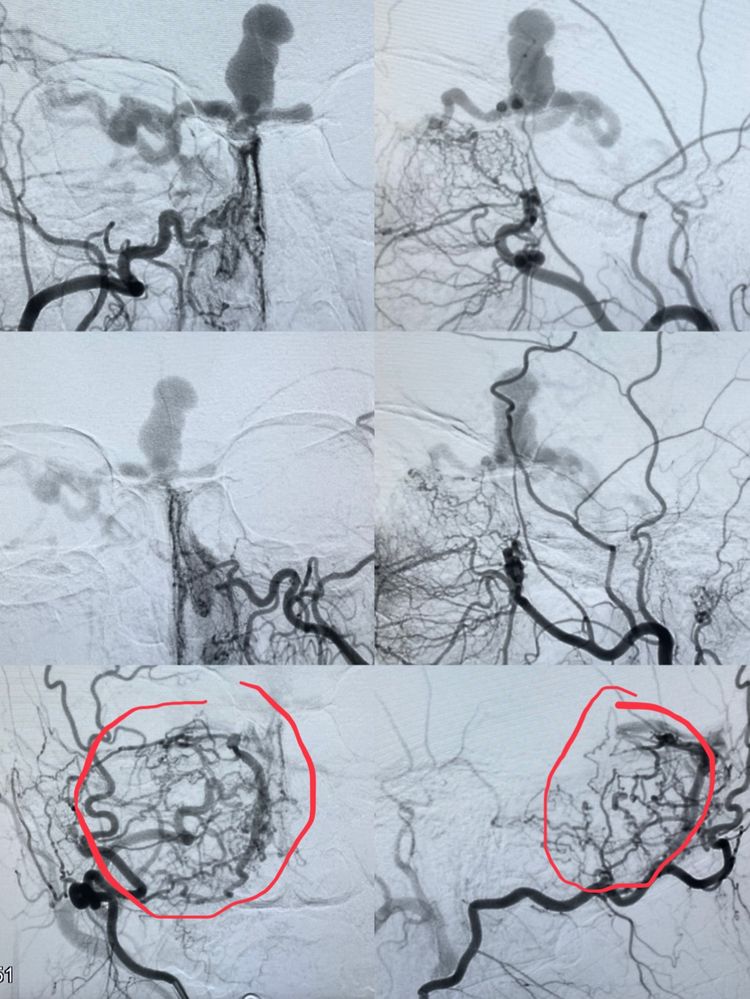

当完成双侧颈内动脉造影后我们发现,不是最初的诊断;

居然是一个前颅窝的硬脑膜动静脉瘘,供血来于双侧眼动脉的脑膜组。

我们认为的动脉瘤其实是引流静脉的球形扩张!

放完滤器、全身麻醉。首先要做一个全面的脑血管造影,特别是硬脑膜动静脉瘘的患者一定要做双侧颈内、外和椎动脉造影,必要时超选到造影。

这不,发现问题了:除了双侧眼动脉供血前颅窝的瘘以外,双侧颌内动脉分支也参与;而且居然又发现了一个后颅窝的瘘。这个后颅窝的瘘可以叫天幕区硬脑膜动静脉瘘吧!虽然没有出血,但可以看出来和前颅窝的瘘具有共同特点:皮层引流且引流不畅(静脉越来越多越来越细)。

这是一种危险结构,容易出血。所以,要干预!

我们首先经眼动脉注胶治愈了前颅窝的硬脑膜动静脉瘘,然后又经过脑膜动脉分支治愈了后颅窝的动静脉瘘。